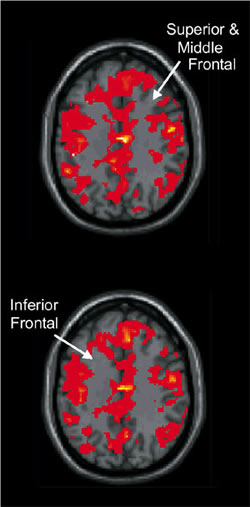

When smokers abstain from cigarettes, there is greater blood flow as measured by fMRI—meaning their brains have to work harder—to perform the same working memory task.